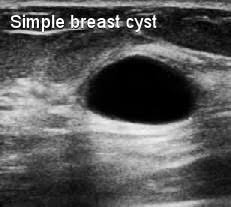

They can also occur in postmenopausal women taking hormone therapy. If the cyst comes back it may be evaluated again with mammogram and ultrasound and it can be drained again. On ultrasound a complex breast cyst will basically be treated in terms of internal echoes presence or absence of posterior enhancement thin septations and a thickened or irregular wall.

The cyst can be then be drained with a fine needle. For simple cysts no treatment is needed unless the cyst is especially large uncomfortable or painful. But the results of the ultrasound can influence the strategy for follow-up evaluation or treatment.